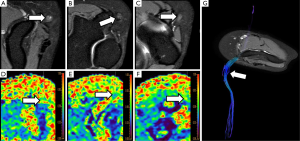

DTI has the added value to perform 3D reconstructions of PN. For PN injuries, 3D neurographic reconstructions may represent the structure of the damaged nerve. This representation may be useful for surgeons for treatment planning and assessment of the relationship of PN with neighboring structures (Figure 7). In cases of severe PN damage, a decrease of FA values under the determined threshold in the software for its 3D representation, may lead to an underestimation of its structure (40).

Radiation induced brachial plexus damage in oncological patients is another not uncommon clinical scenario (51). In spite of new modulated radiation therapy techniques for head and neck or breast cancer treatment, post-radiotherapy brachial plexus neuropathy has to be considered when oncological patients with suspicion of brachial plexus involvement are evaluated (Figure 8). DWN shows nerve root thickening with increased signal intensity on high b values and also increase of ADC. Moreover, in these patients, DWI has the added value to rule out malignant infiltration of brachial plexus which typically shows lower ADC values with or without associated soft tissue abnormalities. Besides, DTI through 3D neurographic reconstructions is able to demonstrate infiltration, disruption or displacement of the involved nerve roots (43).

Brachial plexus roots and trunks on DTI after a direct or an indirect trauma demonstrate similar variations of FA or RD values to those described above for PN injuries. Neuropraxia of brachial plexus roots will show a decrease of FA values, due to loss of fiber organization, and increase of RD values (Figure 9). The amount of these changes is directly related to the severity of the neural damage and may be consider as a complementary tool to the clinical and electrophysiological evaluation (52).

The sciatic nerve is the major PN in the body, both for its length and its width. Clinical manifestations of sciatic nerve are common, and are challenging to study with MRI due to its length. Sciatic nerve entrapment usually occurs at a pelvic level, the so-called piriformis syndrome, due to a mass compression, trauma or a compression neuropathy (68,69). According to some authors, the existence of a piriformis hypertrophy, as may occur in runners, or accessory muscle can condition compression on the sciatic nerve and justify the symptoms (70,71). Morphological MRI is able to determine the anatomy of the piriformis muscle and its relation with the sciatic nerve, bur may not always show enough accuracy for detecting changes at the sciatic nerve that justify the symptoms. However, DWN allows multiplanar reconstructions that facilitate the qualitative assessment of the nerve in almost its entire length, detecting differences in signal intensity of the sciatic nerve in comparison to the contralateral, healthy one (Figure 13). Furthermore, at the point of nerve compression, ADC shows higher values than in the rest of the nerve, presumably due to the coexistence of edema (40,72). 3D neurographic reconstructions from DTN data may help in the assessment of the relationship between sciatic nerve and piriformis muscle and its several variants that may help clinicians to establish a most certain diagnosis of this underdiagnosed entity (73) (Figure 14).

After surgical repair, FA values should progressively increase at the distal site of the nerve injury reflecting restoration of nerve continuity. Changes in RD may depend on the severity of the previous nerve trauma, which may induce distal nerve damage due to the disruption of vasa nervorum. In this field, the recovery (with increase) of AD values at the distal segment would be a potential biomarker of axonal flow restoration. However, further studies are needed to confirm the usefulness of this approach. DTN studies may also assess the existence of growing neural fibers during the regeneration process (80).